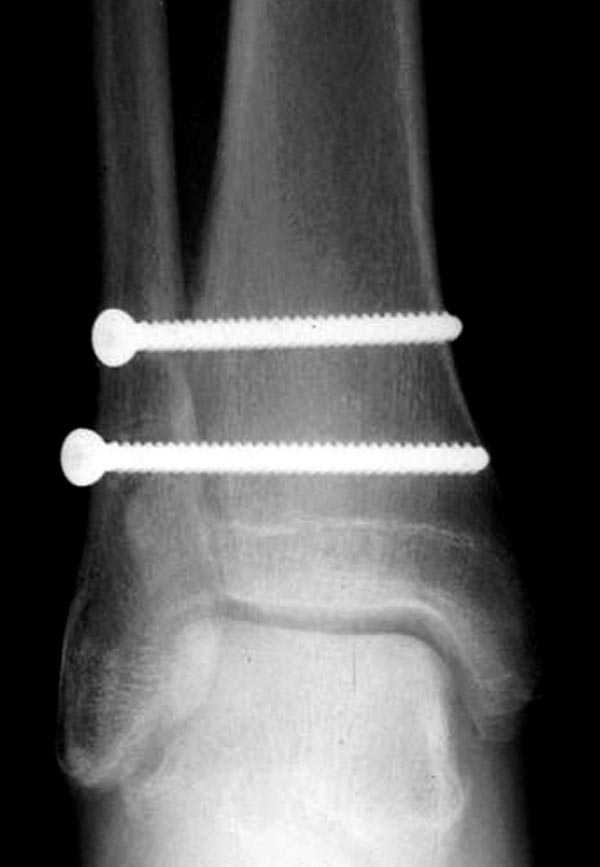

Две параллельных шурупа создают условия для сращения мембраны и синдесмоза, 8 недельный срок достаточен, и можно удалить фиксаторы.

Глубокоуважаемый Якоб Одесскиий! Увы, но из снимков голеностопа возможно предоставить только приложенный, боковая проекция в первичном сообщении. Спасибо за указание возможного повреждения голеностопа, но напомню, что главный вопрос топика о неоходимости синтеза малоберцовой кости ПЛАСТИНОЙ. В примерах показанных Джолдасом Кульджановым пластина и вообще вмешательство в область перелома не используется, т.е. его позиция ясна. Вы можете что-то добавить?